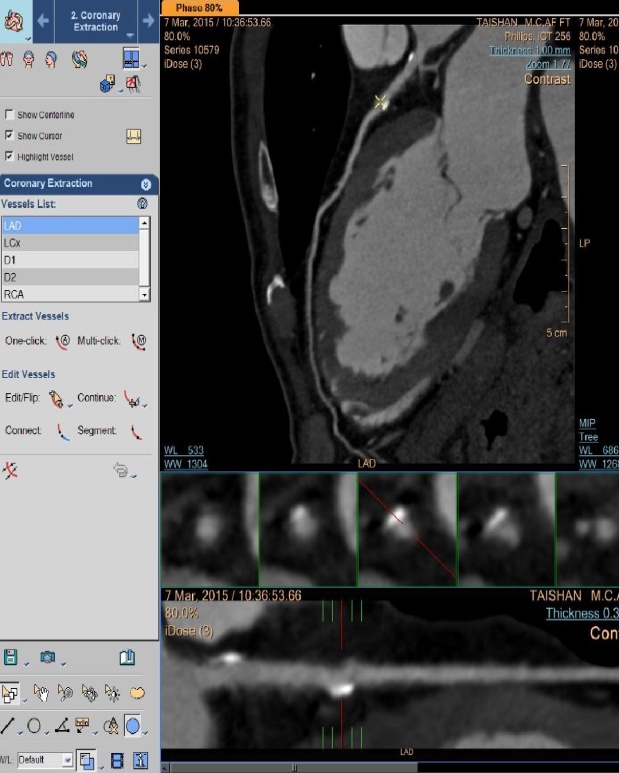

冠状动脉CTA检查是一项用于检查动脉血管是否正常的辅助检查,通过注射造影剂做血管造影可得CT血管造影,用于判断大动脉炎、动脉硬化闭塞症、主动脉瘤及夹层 等病症,用于帮助临床诊断。是冠心病早期筛查的首选,冠脉PCI、搭桥随访观察,冠脉钙化精确测定的最优选择。